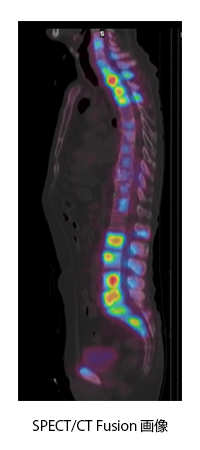

全身の骨の状態を見る検査です。この検査は、午前中に検査用の薬を注射します。撮像は午後行います。撮像時間は約30分です。使用する薬は、主に尿中に排泄されるため、尿がたまっていると膀胱周辺の骨の情報がわかりにくくなります。そのため、撮影直前にお手洗いに行っていただきます。